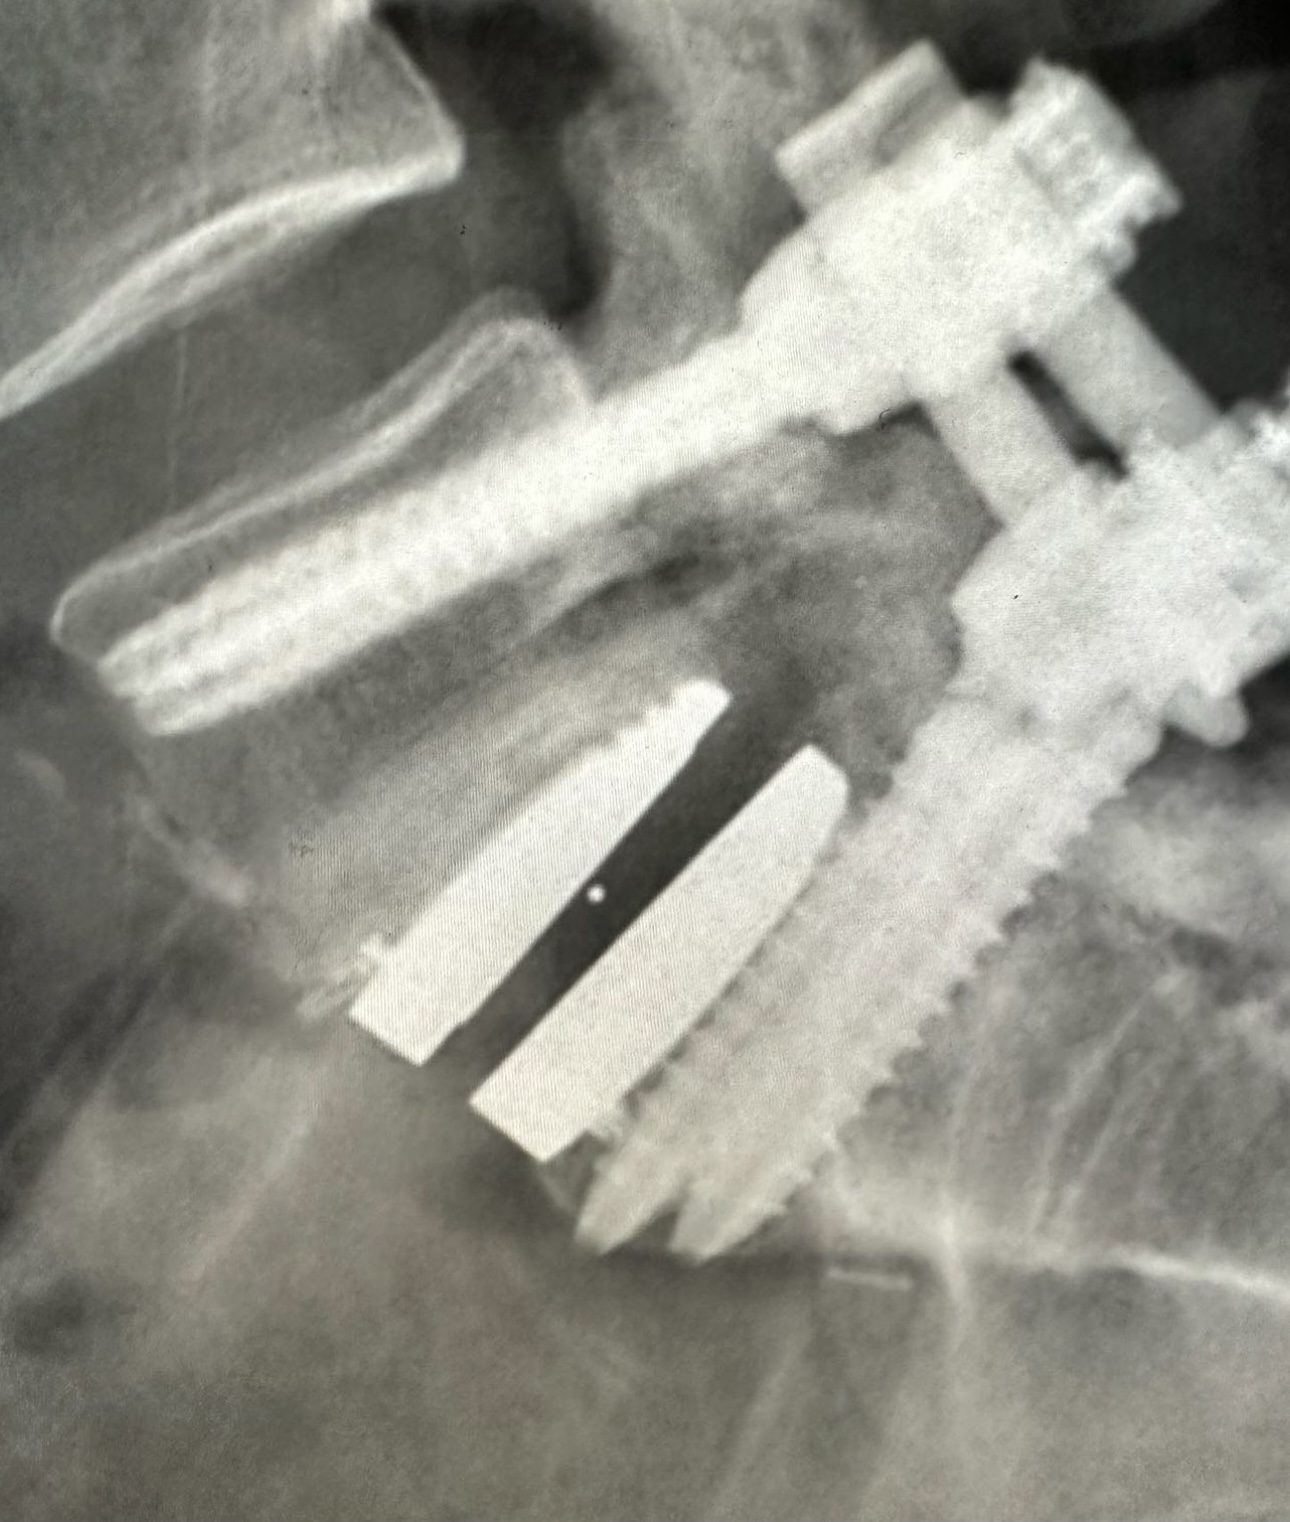

46 YO physician had a degenerative disc 5 years ago. Back pain refractory to conservative therapy. The doctor appropriately checked the facets which you see in the first picture and they are healthy. She is a good candidate for disc replacement. Her facets became arthritic at the index level. L5-S1 over several years and pain returned. The surgeon decided to fuse over the disc from her back. The implant chosen has a mobile core which I personally do not like at L5-S1. Also appropriate however in my experience I find a high incidence where the fusion does not heal. See the videos where I demonstrate why. The implant usually needs to be removed and fused in the front. She also had issues at tbd disc above. So here I used a fixed core implant above at L4-5.